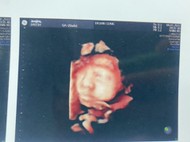

ทีมเมษา ขอดูภาพซาวด์ต้าวตัวเล็กหน่อยค่ะแม่ๆ

ขอดูภาพซาวด์ต้าวตัวเล็กหน่อยค่ะแม่ๆ

ซาวตอน28+1